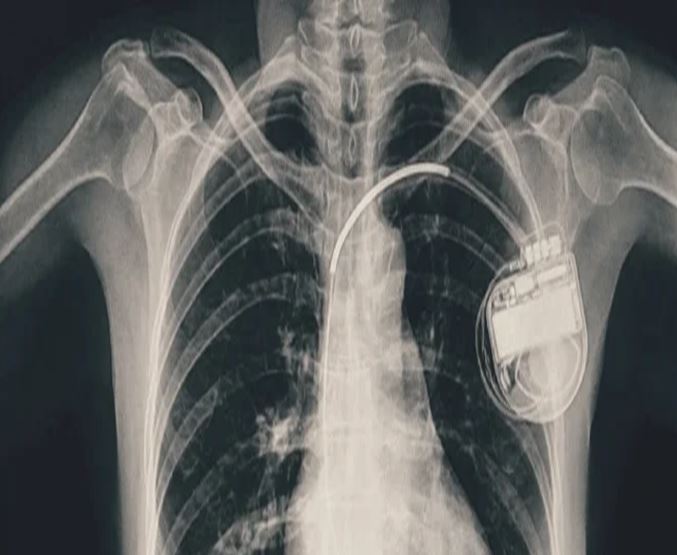

भोपाल। भोपाल मेमोरियल अस्पताल एवं अनुसंधान केंद्र (बीएमएचआरसी) के कार्डियोलॉजी विभाग ने एक दुर्लभ और चुनौतीपूर्ण चिकित्सा उपलब्धि हासिल की है। यहां 13 वर्ष की गैस पीड़ित आश्रित बालिका को इमरजेंसी में डुअल चेंबर पेसमेकर लगाकर उसकी जान बचाई गई। अब बालिका की हालत बेहतर है और उसे अस्पताल से छुट्टी दे दी गई है। यह प्रक्रिया सहायक प्रोफेसर डॉ. अमन चतुर्वेदी और उनकी टीम द्वारा सफलतापूर्वक की गई।

पेसमेकर एक छोटा उपकरण होता है, जो दिल की धड़कन को नियंत्रित करता है। यह दिल को सही गति से धड़कने में मदद करता है। सिंगल चेंबर पेसमेकर हार्ट के सिर्फ एक चेंबर को इलैक्ट्रिक सिग्नल देता है, जबकि डुअल चेंबर पेसमेकर दिल के दो भागों-ऊपरी (एट्रियम) और निचले (वेन्ट्रिकल) चेंबरों को दोनों को सिग्नल भेजता है, जिससे दिल की धड़कन और भी प्राकृतिक तरीके से चलती है। बच्ची के मामले में डुअल चेंबर पेसमेकर इसलिए लगाया गया क्योंकि उसकी स्थिति अधिक जटिल थी और बेहतर तालमेल के लिए दोनों चेंबर तक एकसाथ सिग्नल देना ज़रूरी था।